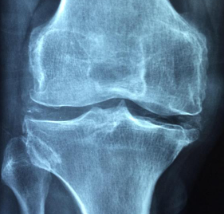

- 퇴행성 관절염 : 퇴행성 관절염은 가장 흔한 관절염의 유형으로, 연골이 점차 닳아 없어지면서 발생합니다. 연골은 관절을 보호하고 부드럽게 움질일 수 있도록 돕는 역할을 합니다. 퇴행성 관절염은 나이가 들면서 자연스럽게 발생할 수 있지만, 외상, 비만, 과체중, 과도한 운동 등도 원인이 될 수 있습니다.